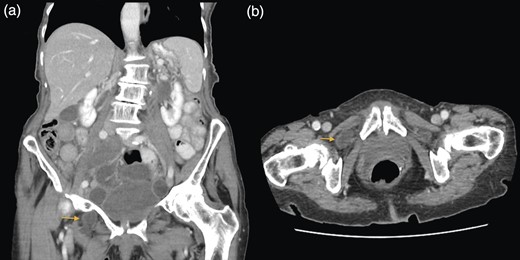

A 88-year-old woman presented to the ED with abdominal pain, vomiting, right hip pain and diarrhoea. Medical co-morbidities include ischaemic heart disease, hypertension and bilateral osteoarthritis of the hip. Her surgical history includes three Caesarean sections, open cholecystectomy, umbilical hernia repair and left mastectomy for breast cancer. A computed tomography (CT) abdomen revealed small bowel obstruction due to the right OH (Fig. 1) and evidence of a small left OH. A trial of conservative management was made for patient due to her age, multiple co-morbidities and patient's wishes. Bowel obstruction resolved with conservative management. The patient re-presented 1 month later with small bowel obstruction and pain radiating down medial left leg. There were no clinical signs of intestinal ischaemia. Abdominal x-ray was consistent with small bowel obstruction (Fig. 2) and CT abdomen revealed transition point at left OH (Fig. 3). A decision was made to proceed with midline laparotomy and bilateral OH repair. Intra-operatively, there was a large right OH containing a small bowel, which was reduced, and a bard polypropylene mesh plug inserted into the defect and fixed with prolene interrupted sutures. The left OH was smaller and was repaired primarily with prolene. The patient made an unremarkable recovery, and she was discharged 3 days after the operation. No recurrence was noted within a year of follow-up.

(a and b) Small bowel obstruction secondary to a left OH. (a) Coronal and (b) axial.